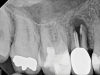

Other common risks associated with post placement include the occurrence of root fracture, perforation, and apical leakage as well as the development of caries (Figure 1 through Figure 3).9 How the post space is prepared significantly affects the ability of the root canal filling material to create a seal.11 Apical leakage increases in correlation with the amount of gutta percha removed from an endodontically treated tooth, increasing the risk of reinfection.11 The risks of fracture and perforation must also be seriously considered. After the performance of endodontic treatment alone, furcation-side dentin thickness in the distal roots of mandibular molars has been shown to be less than 1 mm in more than 80% of teeth.12 After preparation of the post space, the remaining dentin thickness in the buccal roots of premolars has been shown to be often less than 1 mm.13 The remaining thickness of the root dentin after endodontic and post placement procedures is the factor most highly correlated with future resistance against root fractures.13 These anatomic studies underscore the need for judicious preparation, and the risks of post placement underscore the need for careful case selection.

(3.) A radiograph of a root fracture associated with a threaded post, cone-beam computed tomography views of a perforation associated with a post, and a radiograph demonstrating evidence of apical leakage associated with posts, respectively.

Figure 3